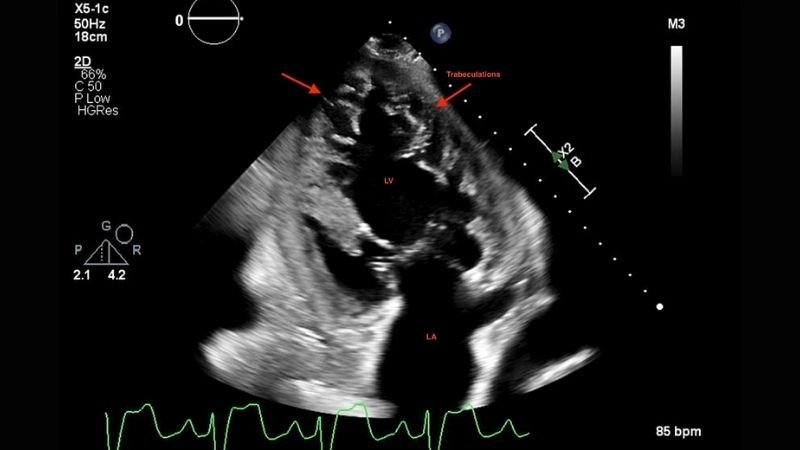

Images visual examples of Left Ventricular Non-compaction Cardiomyopathy

This abnormal structure weakens heart function, disrupts blood circulation, and can lead to life-threatening complications if not diagnosed early.